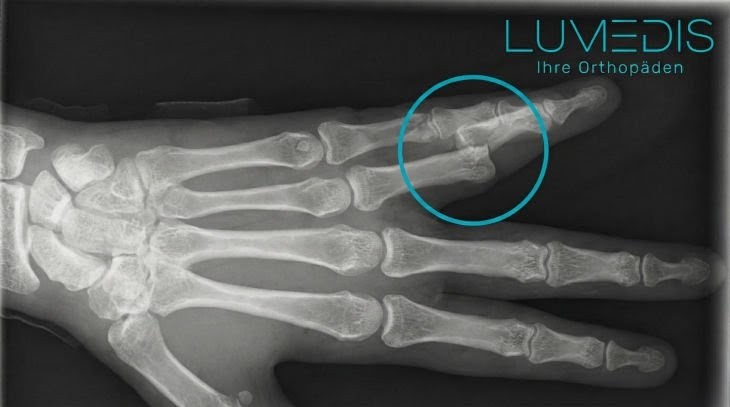

So sieht ein gebrochener Daumen im Röntgenbildaus:

Röntgenbild eines gebrochenen Ringfingers (Nagelkranzfraktur)